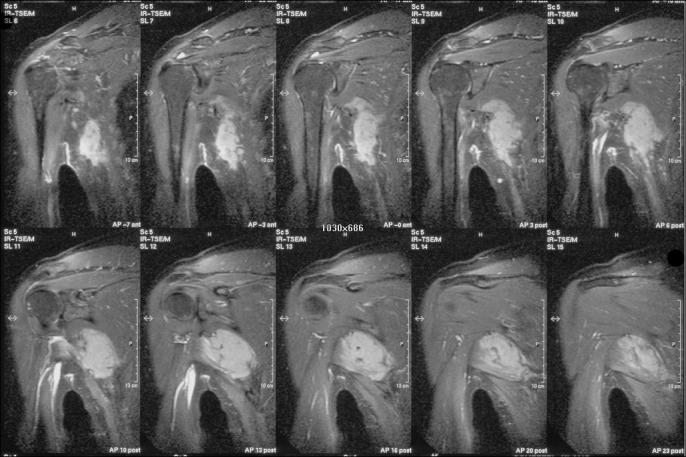

Surgery was performed on 7 patients with extraabdominal desmoid fibromatosis between August 1998 and May 2007. MRI examination as well as biopsy was carried out in all cases. All patients were operated on; the mean follow up was 4 years (1-7). Upon follow up, every patient has undergone clinical and MRI examination.

The early diagnosis of the disease is of utmost importance to the success of the outcome. MRI examination and biopsy are mandatory. Surgery is the therapy of choice. The recurrence rate is high and is linked to the difficulty of recognition of the exact infiltrative extent of the tumour. This necessitates a close follow-up.

1998年8月至2007年5月期间,对7例腹壁外韧带样纤维瘤病患者进行了手术。所有病例均进行了MRI检查及活检。所有患者均接受了手术治疗;平均随访时间为4年(1 - 7年)。随访期间,每位患者均接受了临床及MRI检查。

疾病的早期诊断对治疗结果的成功至关重要。MRI检查和活检是必需的。手术是首选治疗方法。复发率较高,且与难以识别肿瘤的确切浸润范围有关。因此需要密切随访。